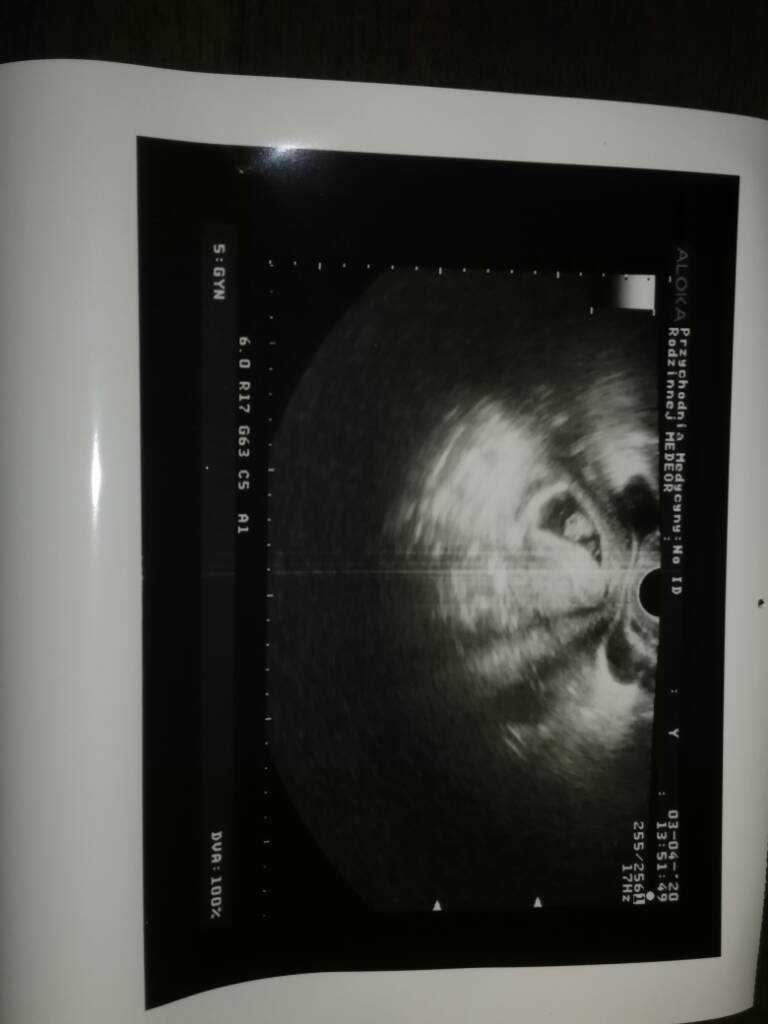

Wracam mega szczęśliwa od pani doktor, jest serduszko, śliczny zarodek mówiła że 7-8 tydzień. Termin 10 listopad. Dziękuję za wsparcie i wiare, że wszystko będzie dobrze. Pani doktor narazie przyjmuje tylko prywatnie więc i tak do niej będe chodzić. Za tydzień kolejna wizyta z wynikami badań i będzie 4 tygodnie zwolnienia z pracy. Wstawiam fotke naszego maleństwa Zobacz załącznik 1101027

Gratulacje, wspaniala wiadomoscWracam mega szczęśliwa od pani doktor, jest serduszko, śliczny zarodek mówiła że 7-8 tydzień. Termin 10 listopad. Dziękuję za wsparcie i wiare, że wszystko będzie dobrze. Pani doktor narazie przyjmuje tylko prywatnie więc i tak do niej będe chodzić. Za tydzień kolejna wizyta z wynikami badań i będzie 4 tygodnie zwolnienia z pracy. Wstawiam fotke naszego maleństwa Zobacz załącznik 1101027